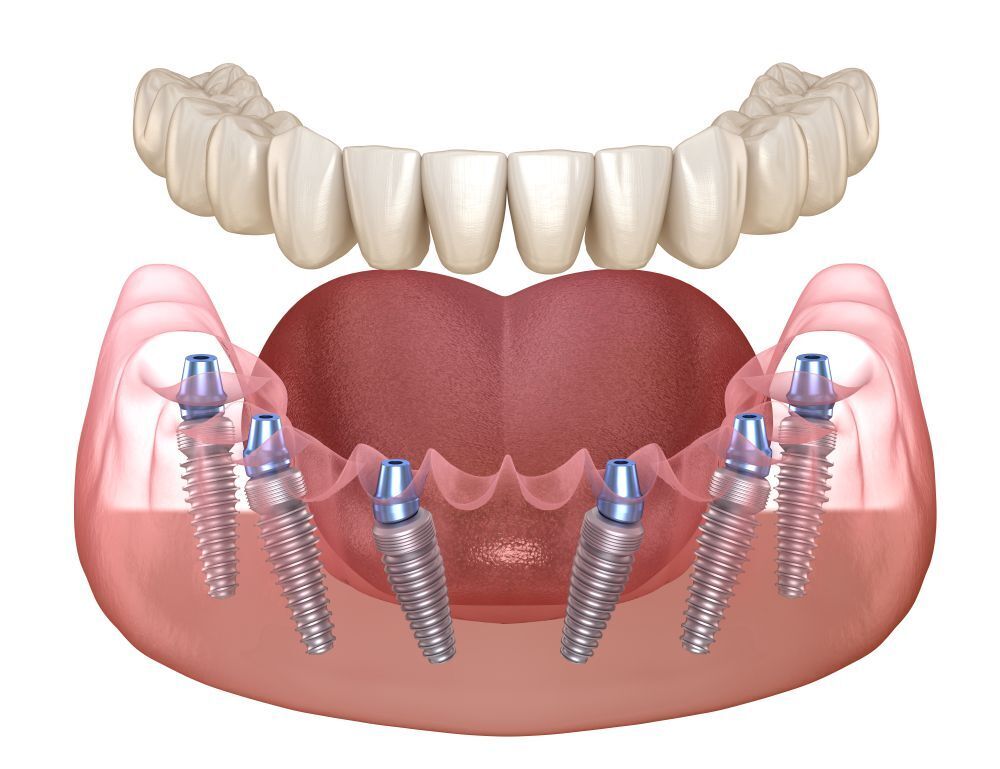

Чем мотивируют, кость тонкая.

заметьте, делают все наискосок. До Рязанских профессоров и лоботрясов это не доходит